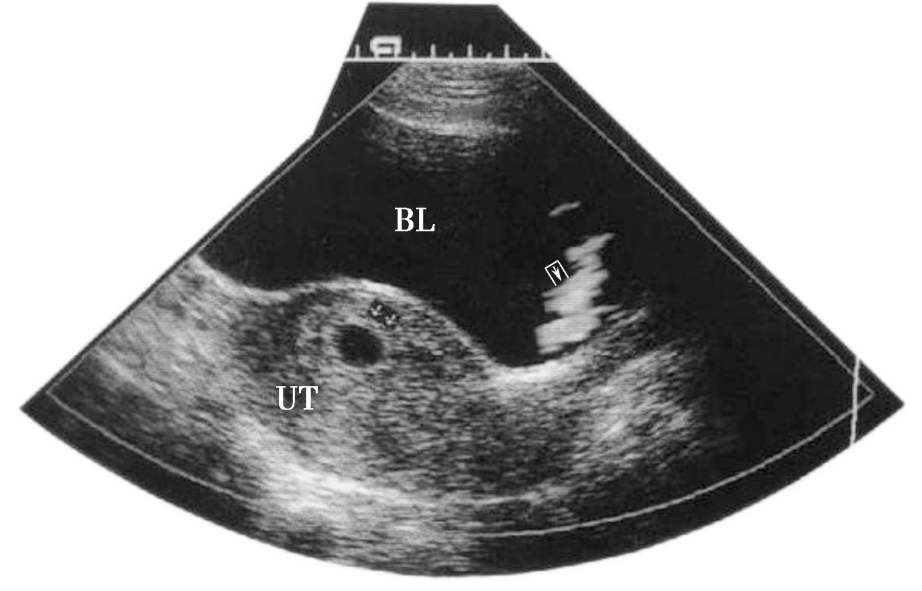

2.超声检查 妊娠早期超声检查的主要目的是确定宫内妊娠,排除异位妊娠和滋养细胞疾病,估计孕龄,排除盆腔肿块或子宫异常;若为多胎,可根据胚囊的数目和形体判断绒毛膜性(图5-1)。停经35日时,宫腔内见到圆形或椭圆形妊娠囊(gestational sac,GS);妊娠6周时,可见到胚芽和原始心管搏动。停经14周,测量胎儿头臀长度(crown-rump length,CRL)能较准确地估计孕周,矫正预产期。停经9~14周B型超声检查可以排除严重的胎儿畸形,如无脑儿。B型超声测量指标有胎儿颈项透明层(nuchal translucency,NT)和胎儿鼻骨(nose bone)等,可作为孕早期染色体疾病筛查的指标。彩色多普勒超声可见胎儿心脏区彩色血流,可以确诊为早期妊娠、活胎。

图5-1 早孕期B型超声图像

妊娠7周见妊娠囊 妊娠8周1天测量头臀长度